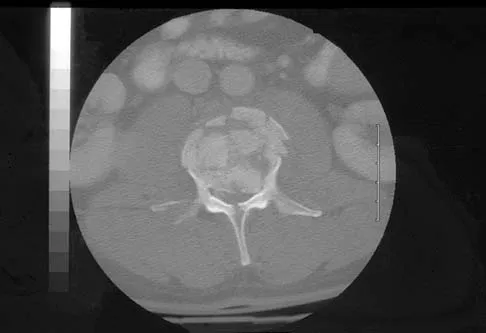

A 46-year-old man has incomplete paraplegia after being involved in a motor vehicle accident. The CT scan shown in Figure 5 reveals marked canal compromise. What is the most appropriate management to improve neurologic status?

Explanation

According to a study by the Scoliosis Research Society, the use of anterior decompression is most predictable for improving neurologic status. This is particularly true of bowel and bladder functional loss. Laminectomy is contraindicated because it further destabilizes the spine. Posterior instrumentation and indirect reduction through distraction and ligamentotaxis only incompletely decompress the compromised canal and are successful only if performed within 48 hours of injury. While some improvement may occur with closed management, the amount of recovery is less than that achieved with surgical decompression. A posterior approach and instrumentation may be added to the anterior decompression based on the characteristics of associated injuries to the posterior element. Gertzbein SD: Scoliosis Research Society multicenter spine fracture study. Spine 1992;17:528-540. Garfin SR, Vaccaro AR (eds): Orthopaedic Knowledge Update: Spine. Rosemont, IL, American Academy of Orthopaedic Surgeons, 1997, pp 197-215.